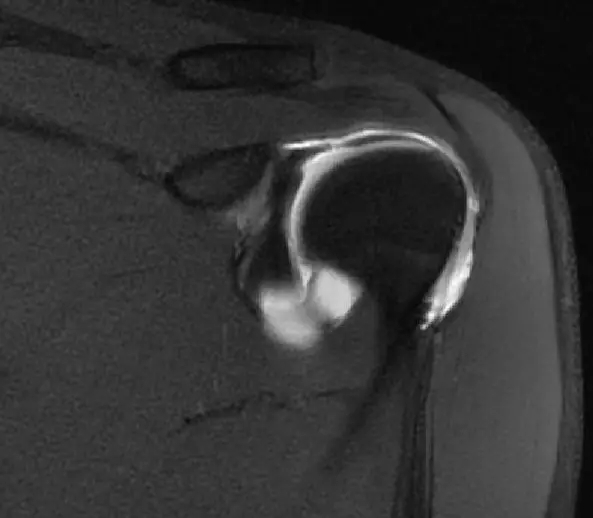

这张片子可以看到上盂唇及肱二头几件长头止点,盂唇高信号的特点,质地比较均一,相对比较尖锐,边界比较清楚

此片可以看到冈上肌腱。